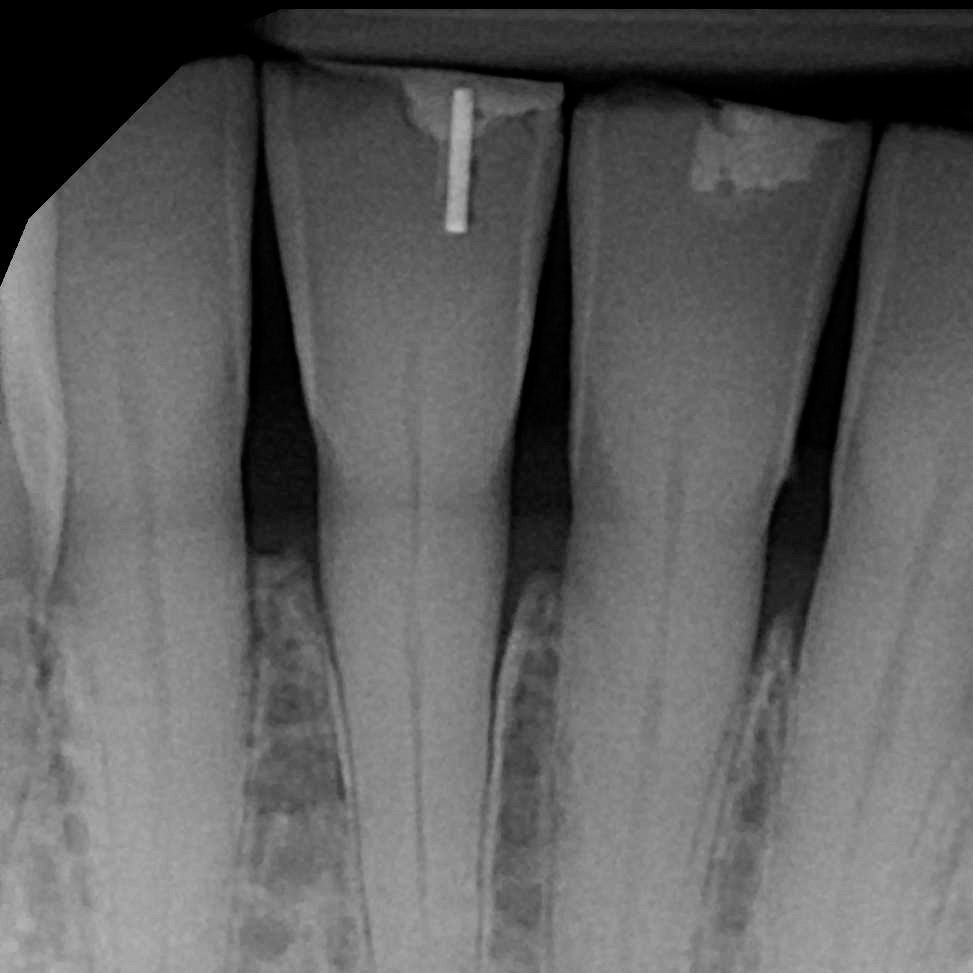

Add Floss to Pin

Be sure to attach floss to the handle of the pin to ensure it is not swallowed or aspirated during the procedure. See the picture above.